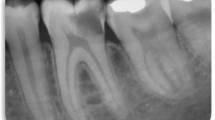

The diagnostic criteria of irreversible pulpitis included (1) spontaneous pain, night pain, persistent pain, or pain on biting and chewing after cold and heat stimulation, (2) clinical examination with percussion pain or dental pulp temperature test can cause sustained pain, and (3) radiograph examination of apical peritubular dentin gap was normal or widened, or small area low-density shadow was seen19. A tooth had to meet all inclusion criteria and at least one criterion of irreversible pulpitis to be included in the study.

A case was considered clinically successful if there was no history of spontaneous pain or discomfort (except during the first few days after treatment), the tooth was functional, and there was no pain or discomfort when chewing or eating, there was a positive response to the cold test, no tenderness to percussion or palpation, normal grade I mobility, and the soft tissues around the tooth were normal with no swelling or sinus tract. The case was considered radiographically successful without internal or root resorption. Persistent severe spontaneous pain, tenderness to percussion, development of a sinus tract, swelling, or a negative response to cold testing was considered a clinical failure; intraradicular or extraradicular pathosis on the recall radiograph was considered a radiographic failure, and root canal treatment was initiated in such cases20.

The dentin bridge formation on the treated pulp section indicates viability and pulp healing capacity and reflects the formation of a protective barrier on the pulp. It has been suggested that dentin bridge formation is an important indicator of treatment success35. However, Taha et al.36 assessed the effects of pulpotomy in immature permanent teeth with carious pulp exposure and found dentin bridge formation in 25% of teeth at 1-year follow-up. Mass et al.37 followed up on the status of the immature permanent teeth treated with partial pulpotomy for carious pulp exposure for 10 years, finding a dentin bridge formation in only 58% of the teeth. The present retrospective analysis of 42 successfully treated teeth also showed dentin bridge formation in 71.4% of teeth (30/42), and treatment success was also achieved in several teeth without dentin bridge formation.